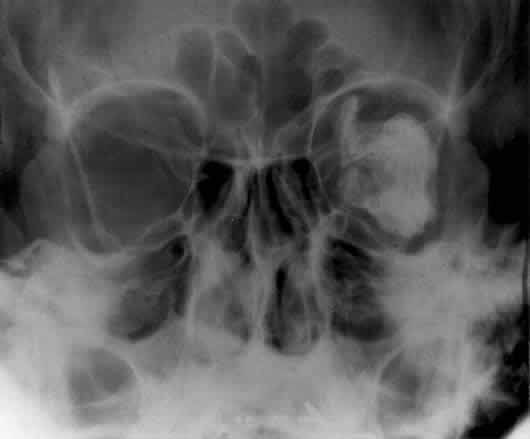

Bony destruction usually results from a rapidly growing process such as a tumor of the lacrimal gland or paranasal sinuses (Fig. 12). Sinusitis or a mucocele can also cause bone destruction or dehiscence of the orbital bones. Mucoceles most often originate in the frontal and ethmoid sinuses, and destruction of bone is noted radiographically in 70% of cases24 (Fig. 13). Encephaloceles may also cause a disruption in the orbital bones, usually superomedially. Neurofibromatosis is associated with dysplasia that can involve large segments of the greater wing of the sphenoid. Pulsating exophthalmos may be a clinical finding.

Fig. 13. Frontal sinus mucocele extending into the right orbit. The orbital extension was responsible for downward displacement of the globe in this patient. The frontal sinus is the most frequent origin for mucoceles.